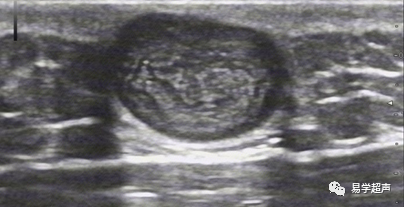

Lee DH, Yoon CS, Lim BJ, Lee HS, Kim S, ChoiAL, Kim S. Ultrasound Feature-Based Diagnostic Model Focusing on the"Submarine Sign" for Epidermal Cysts among Superficial Soft TissueLesions. Korean J Radiol. 2019 Oct;20(10):1409-1421.